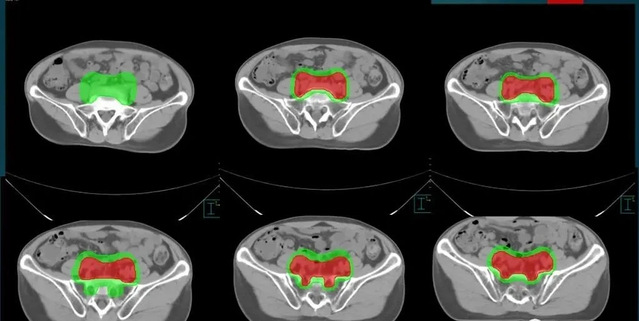

3、靶区勾画及放疗剂量

放疗医生在模拟定位过程获得的CT图像上逐层(30-80层)勾画患者的肿瘤及需要照射的区域,同时还需要勾画出需要保护的正常器官(10-30种)。靶区的确定和放疗剂量、照射次数都有关系,还需要考虑到正常器官。

这个过程,经验丰富的放疗医生需要1-2个小时,复杂情况可能需要4个小时,甚至更长时间。射线就像放疗医生的手术刀,放疗医生需要接受扎实的医学、肿瘤、放疗的专业教育和培训,以及长期的临床实践和经验,一个合格的放疗医生培训时间和外科医生差不多,需要10年以上。

直肠癌靶区勾画示例